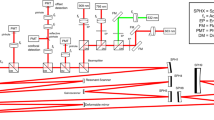

Multimodal imaging equipment

Multimodality imaging combining SD-OCT and PAM allowed for simultaneous or sequential acquisition of structural and functional information with high resolution and depth of penetration. Figure 5 depicts our multimodal imaging system that combines spectral-domain optical coherence tomography (SD-OCT) and photoacoustic microscopy (PAM)39,50. The system, as described by Tian et al., integrates the capabilities of both modalities to provide complementary imaging information36. The SD-OCT component of the system was modified from a commercially available system (Ganymede-II-HR, Thorlabs, Newton, NJ, USA). The system included an additional ocular lens following a scan lens, and a dispersion compensation glass (DCG) was added to the OCT reference arm. For the PAM component, an optical parametric oscillator (OPO) (NT-242, Ekspla Vilnius, Lithuania) served as the illumination source. The OPO offered tunability in wavelength (405–2600 nm) and had a pulse duration of 3–6 ns. The PA signal, generated by endogenous chromophores such as hemoglobin and melanin, was detected by a custom-built needle-shaped ultrasonic transducer (Optosonic Inc, Arcadia, CA, USA) with a center frequency of 27.0 MHz. The transducer was in direct contact with phosphate-buffered saline (PBS) on the rabbit conjunctiva. The PA signal was digitized using a high-speed digitizer (PX1500-4, Signatec Inc., Newport Beach, CA, USA) with a sampling rate of 200 MS/s and amplified using a low-noise amplifier (AU-1647, L3 Narda-MITEQ, NY, USA) with a gain of 57 dB.

Schematic of the experimental setup multimodal photoacoustic microscopy and optical coherence tomography. (a–b) Side and front views of the imaging system. (c) Magnification of the selected area shown in (b). (d) Magnification of the violet area shown in (c), demonstrating schematic of the retina, position of the transducer in contact with conjunctiva and laser beam focus in the retina.

The center laser wavelength for the OCT system was 905 nm, using two superluminescent light-emitting diodes with center wavelengths of 845 nm and 932 nm. The approximate bandwidth estimation is around 220 nm. The imaging depth of the OCT system was 1.9 mm. The aerial lateral resolution of the PAM system was demonstrated to be 4.1 μm, while the SD-OCT system achieved an aerial lateral resolution of 3.8 μm51. The PAM and OCT systems have quantified axial resolutions of 37.0 μm and 4.0 μm, respectively. The laser energy was maintained at approximately half of the ANSI safety limit, measuring around 80 nJ.